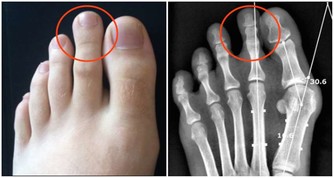

①防癌體檢與一般體檢不同,不同的癌症高危人群,有不同體檢方式可以選擇。比如肺癌,可以選擇胸部低劑量螺旋CT。乳腺癌:鉬靶+超聲。肝癌:超聲+血的甲胎球蛋白檢測。結直腸癌和胃癌、食管癌:腸鏡和胃鏡。